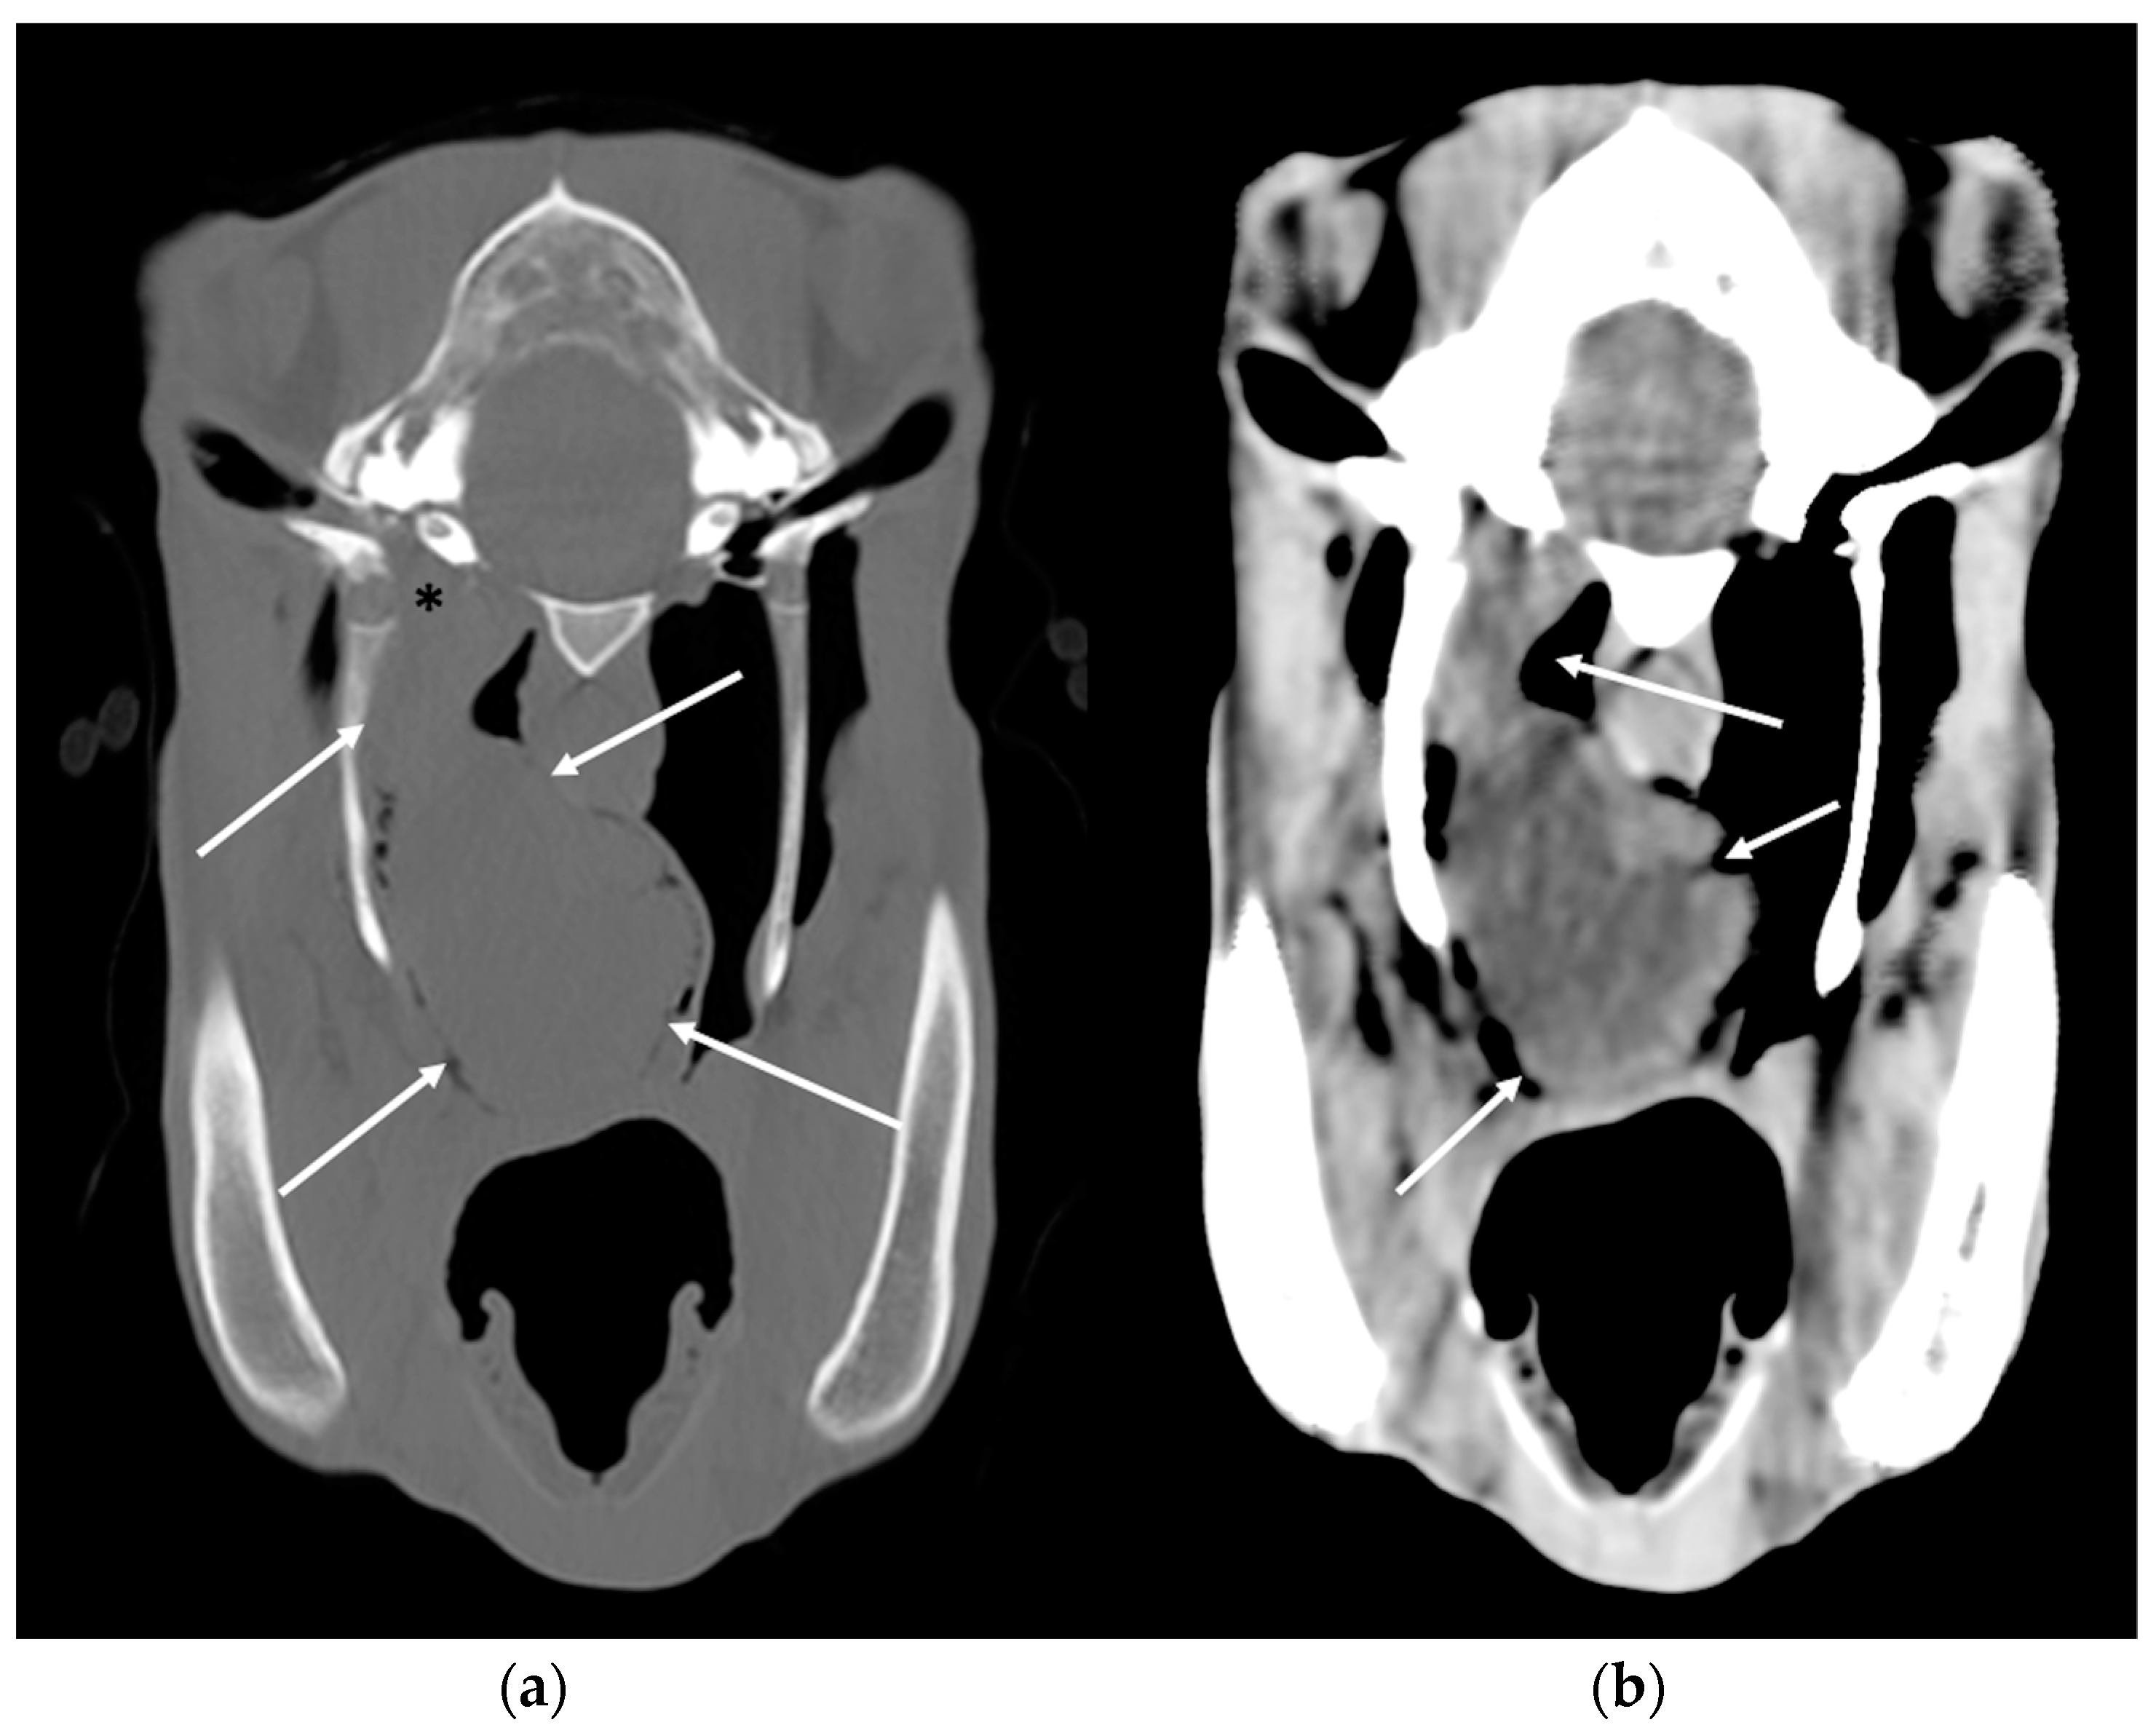

3.4. Temporohyoid Osteoarthropathy